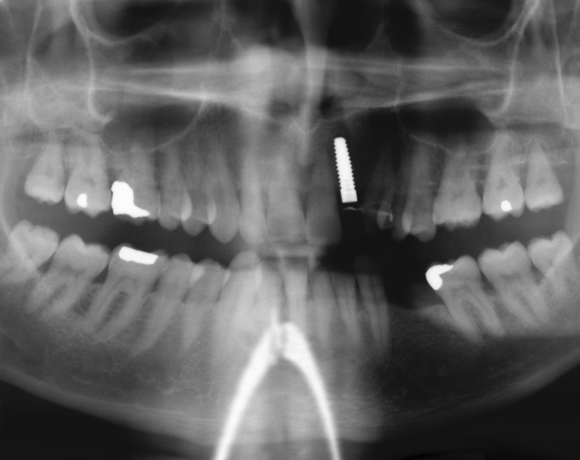

Zeramex Implantat auf Zahn12

Ein Projekt aus dem Jahr 2011

Bei diesem Patienten wurde der nichterhaltungswürdige Zahn 12 mit einem Zerameximplantat versorgt. Nach der Einheilphase wurden auch die Zähne 14 und 13 mit e.max Kronen versorgt